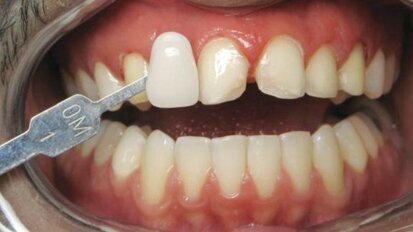

Rendre des facettes unitaires si naturelles qu'elles soient indétectables

Comme les patients vieillissent, les dents antérieures présentent souvent de l'usure, de l'effritement et de la décoloration. Ces ...